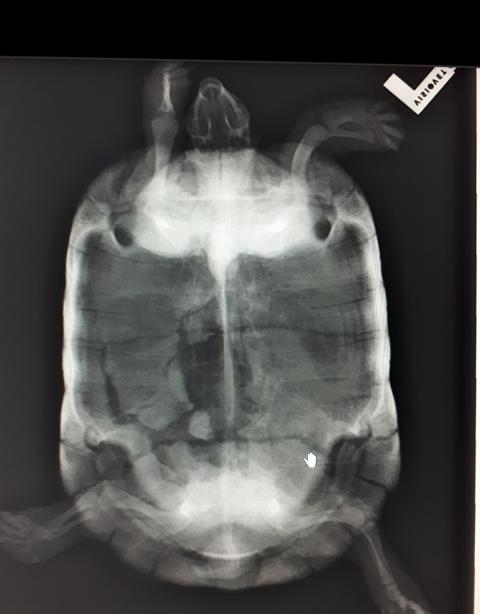

Die Dame wurde nun erst noch einmal ordentlich auf den Kopf gestellt. Bluttests, Röntgen, Herpes und Mykoplasmentest, Wurmuntersuchung und so weiter.

Der Tierarzt vermutete, anhand des Bildes der Verletzung, dass etwas schweres ( z. Bsp. Ein großer Stein) auf den Panzer gefallen ist oder die Verletzung durch einen Hammer verursacht wurde. Was wirklich passiert ist und ob es Tierquälerei oder ein Unfall war, werden wir nie erfahren.

Die Wunde wurde nun erst mal genau untersucht und lose Knochensplitter entfernt. Dabei wurde ein Pilz in der Tiefe entdeckt, der dann auch noch behandelt werden musste.

Trotz allem, was dieses Tier durchmachen musste, waren die Blutwerte überraschend gut und die Nierenwerte Top in Ordnung. Alleine die Leber ist durch die Höchstleistungen, die sie bei der Heilung erbringen musste, leicht angeschlagen.